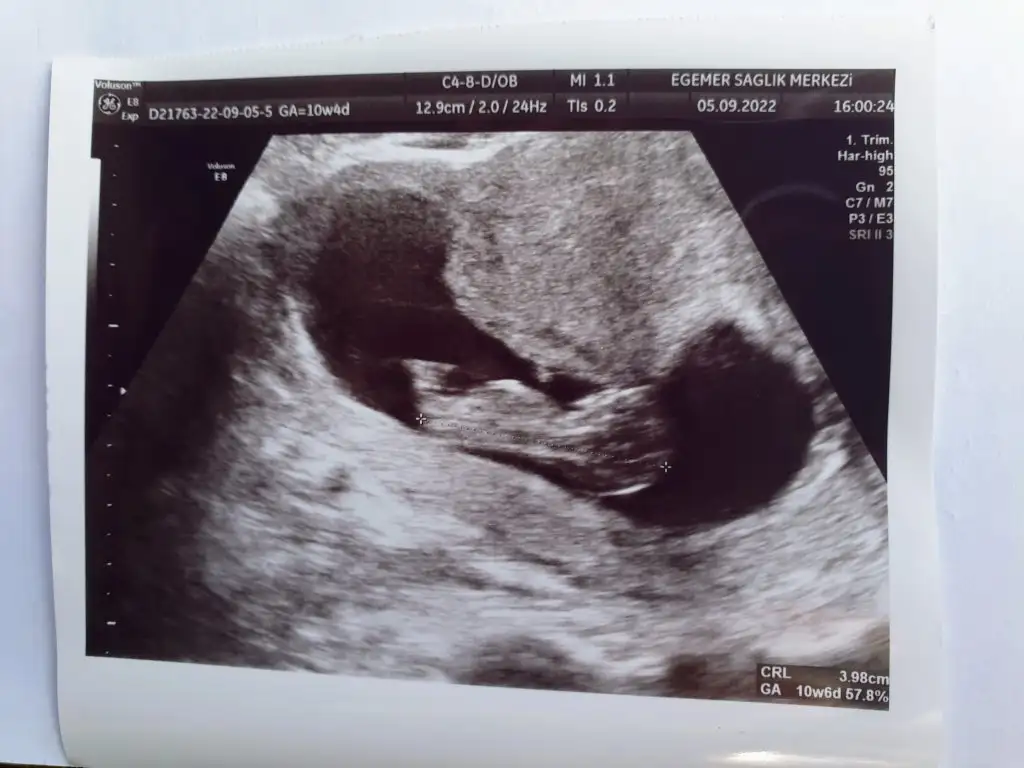

Merhaba bana da tahminde bulunurmusunuz lütfen 🥰🙏 10+4 ve 10+6 karindan ultrason fotolari. 1. Resimdekini pipi zannetmistim meğer ayağiymiş 😅🙈

20220906_175540.webp 20220905_160108.webp